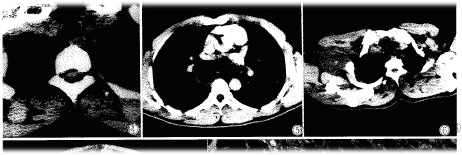

纵隔内神经鞘瘤,除1例位于椎体前方外,其余均位于脊柱两旁,边缘光滑,宽基底与脊柱相连,密度一般均匀(图4),2例呈低密度(类似水样密度)CT值13-19Hu,其余8例密度均匀低于或等于肌肉密度,增强扫描1例无强化(图5),4例不均匀强化。胸椎及肋骨骨质未见明确破坏和吸收,肿瘤未侵入椎管内。

图1腰5椎管内神经鞘瘤椎间盘突出术后二年,腰5右侧神经根增粗,呈圆形软组织密度影。图2颈7椎管内神经鞘瘤,脊髓向前受压变扁,蛛网膜腔增宽扩大。图3颈动脉鞘区偏后神经鞘瘤,增强扫描强化不均匀,血管受压向前移位。图4纵隔神经鞘瘤宽基底与脊柱相连,边缘光滑,密度均匀。图5纵隔神经鞘瘤增强扫描,边缘轻度强化,中心不强化。图6臂丛神经鞘瘤,边缘光滑,密度均匀。图7腹腔恶性神经鞘瘤,肿瘤不规则,密度不均,见大片液化坏死区。图8神经鞘瘤病理见瘤细胞呈栅栏状改变(×40)